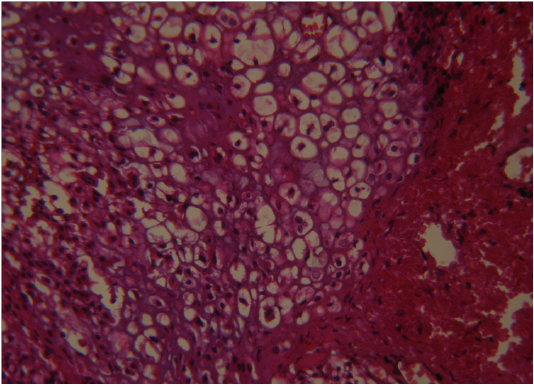

Figure 4

Tumour mass showing pleomorphic chondrocytes with mitotic (arrows) figures (H&E×400)